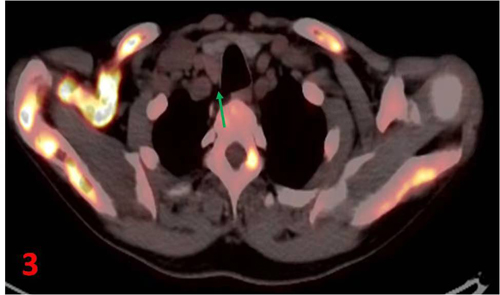

甲狀腺右葉后方見不規(guī)則軟組織密度結(jié)節(jié)(圖3箭),長徑約2.3cm,未見明顯顯像劑攝取增高區(qū)。

全身多發(fā)骨骼異常,符合甲狀旁腺功能亢進(jìn)性骨??;甲狀腺右葉后方結(jié)節(jié),不除外甲狀旁腺來源病變。雙腎及右側(cè)輸尿管上段結(jié)石,右腎重度積水,左腎輕度積水。